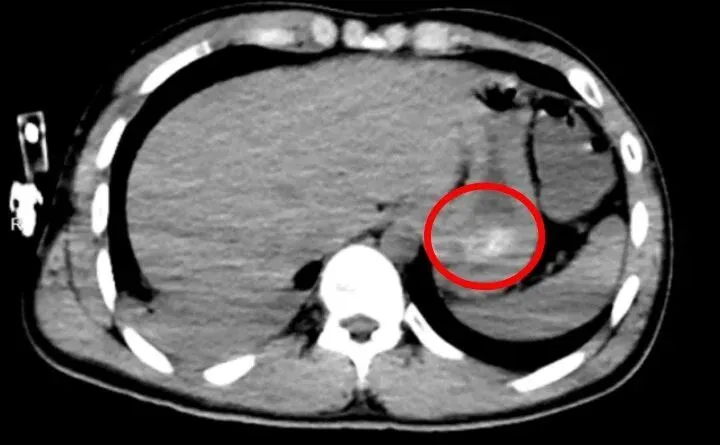

医院中毒医疗救治基地的快速反应团队迅速介入。团队判断,一次性吞服如此大量的药丸,极有可能在胃内形成了常规洗胃无法清除的坚硬“药石”。随后的全腹CT检查证实了这一判断,患者胃底存在大量团块状高密度影,这个“药石”就像一个持续释放毒性的仓库,不断将药物送入血液。同时,CT还显示患者已出现吸入性肺炎,若不尽快清除药石,将面临多器官功能衰竭乃至死亡的风险。